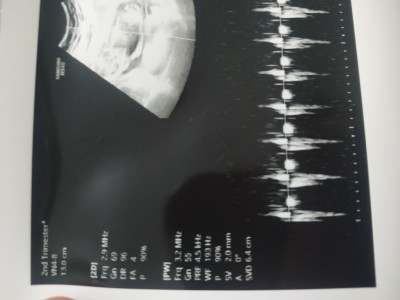

Arkadaşlar sorum yukarda kalp atımini.sormayi.unutuyorum.hep doktora ultrason kağıdında yazıyormus ama nerede bilen varmı ?

Gebelik haftası 15

Şu düzenli siyah çizgiler kalp atışı kalp atışları da iyi :)

Kaç attığını sormayı unuttum ultroson cihazında yazarmis nerede yazıyor tam olarak anlamadım

Orada kaç attığı nerede yazıyor tam olarak biliyormusunuz

Fotoğraf net değil göremiyorum ve fotoğrafın öteki kenarında da yazıyor olabilir. Evham yapma iyi cikmis işte bosver